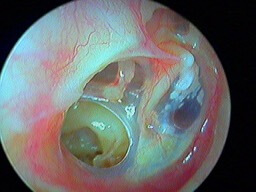

Otite barotraumatique: sang derrière le tympan

L'otite barotraumatique est une atteinte de l'oreille moyenne, due à une variation trop rapide de la pression au niveau de la trompe d'Eustache pour équilibrer. Cela commence par une otite séreuse puis un hémotympan (sang derrière le tympan), et enfin le tympan perce. Les barotraumatismes sont souvent déclenchés dans l'avion (patient(e) enrhumé(e)) ou en plongée sous-marine avec bouteille.